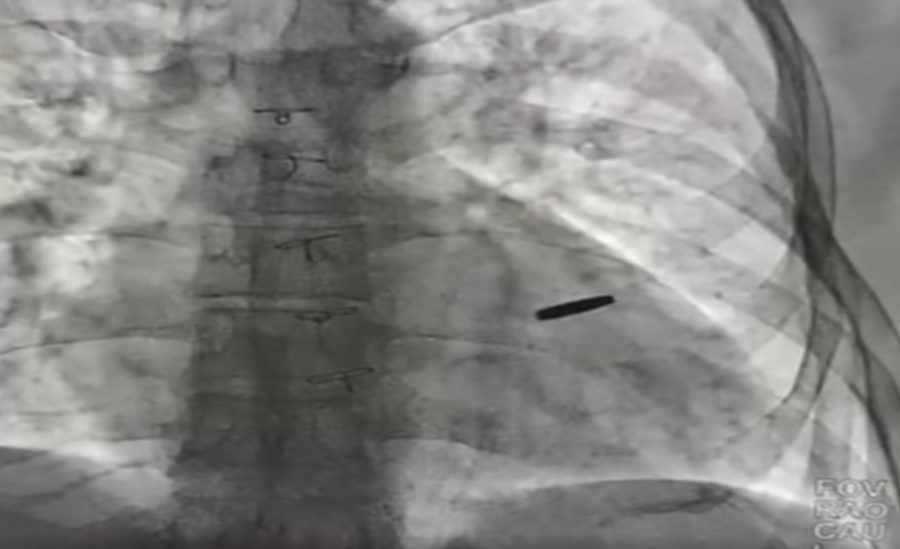

Із серця українського військового в Києві дістали кулю, з якою він прожив три роки в російському полоні.

Про це повідомив директор Інституту серця МОЗ України Борис Тодуров, пише Суспільне.

Військовий захищав “Азовсталь” і пораненим потрапив до російському полону під час боїв за Маріуполь. Три роки він був у неволі, а два місяці тому його обміняли.

“Три роки він був з цієї кулею, прожив. На щастя, вона нічого не пошкодила, зараз ми її видалили, пощастило хлопцю”, — наголосив Тодуров.